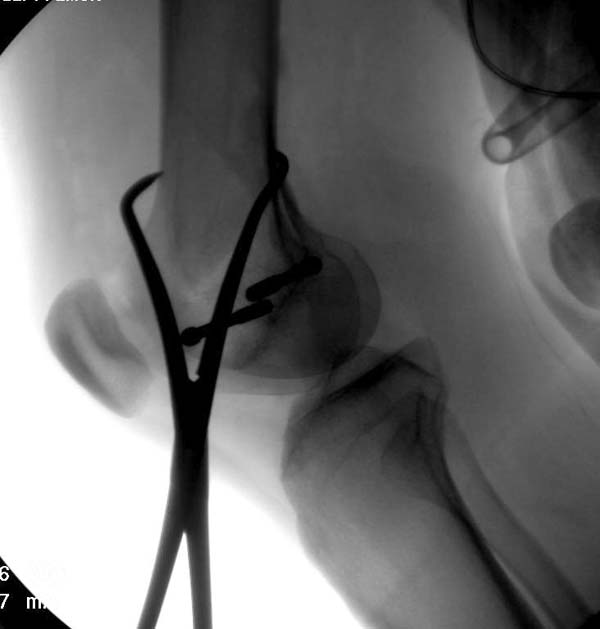

При изолированных переломах можно лечить миниинвазивно каннюлированными винтами, но в большинстве Hoffa компонент сопровождается другими типами перелома дистального бедра. Выбор доступа зависит от расположения фрагментов и большинстве латеральный субвастус доступ подойдет для фиксации перелома.

В данном случае предпочтителен парапателлярный доступ, где необходимо создать лучший обзор к мыщелку. После остеотомии и репозиции фиксацию надо проделать поперечными винтами и дополнительно задней antiglade plate - сделанной из 1/3 tubular plate.

Здесь представлены различные варианты фиксации перелома, а также снимки комбинации перелома с повреждением хряща (12-19). Пластика хряща OsseoFit и установка custom made plate.